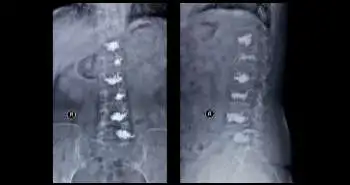

All 28 patients were having severe osteoporosis. The VAS at final follow-up (0.50 ± 0.69) was significantly lower as compared to before surgery (4.93 ± 1.30). There was a significant decrease in the Oswestry Disability Index score at final follow-up, i.e., from 57.39% ± 14.46% to 6.83% ± 15.38%. It was also observed that at the final follow-up the Radiologic evaluation of vertebral height and Cobb angle showed measurable fracture reduction and satisfactory correction of kyphosis. No occurrence of screw loosening or symptomatic complications were seen, only a few cases presented cement leakage (10.3%; cement leakage most common in AO type A3.3) from CICPS.

Polymethyl methacrylate augmented CICPS found to be a safe and effective surgical technique for management of osteoporosis-related vertebral fractures (AO type A). This method also exhibited good clinical outcomes and low complications rates.